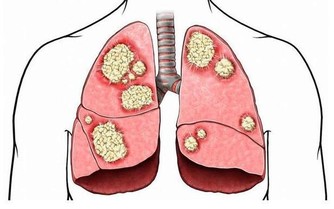

肝區不適:在所有肝病症狀中,肝區不適和肝區疼痛較具有特異性,

出現此類症狀時首先懷疑是肝病引起的,應排除外傷因素。

偶爾正常人也會出現暫時性肝區疼痛不適,比較少見。

肝區不適和肝區疼痛往往與肝腫大壓迫肝包膜有關,隨著病情的轉歸,

肝腫大的加重或減輕,肝區疼痛的性質和程度也不相同。

肝癌一般是進行性加重,主要是肝癌腫瘤不斷增大壓迫肝包膜所致。